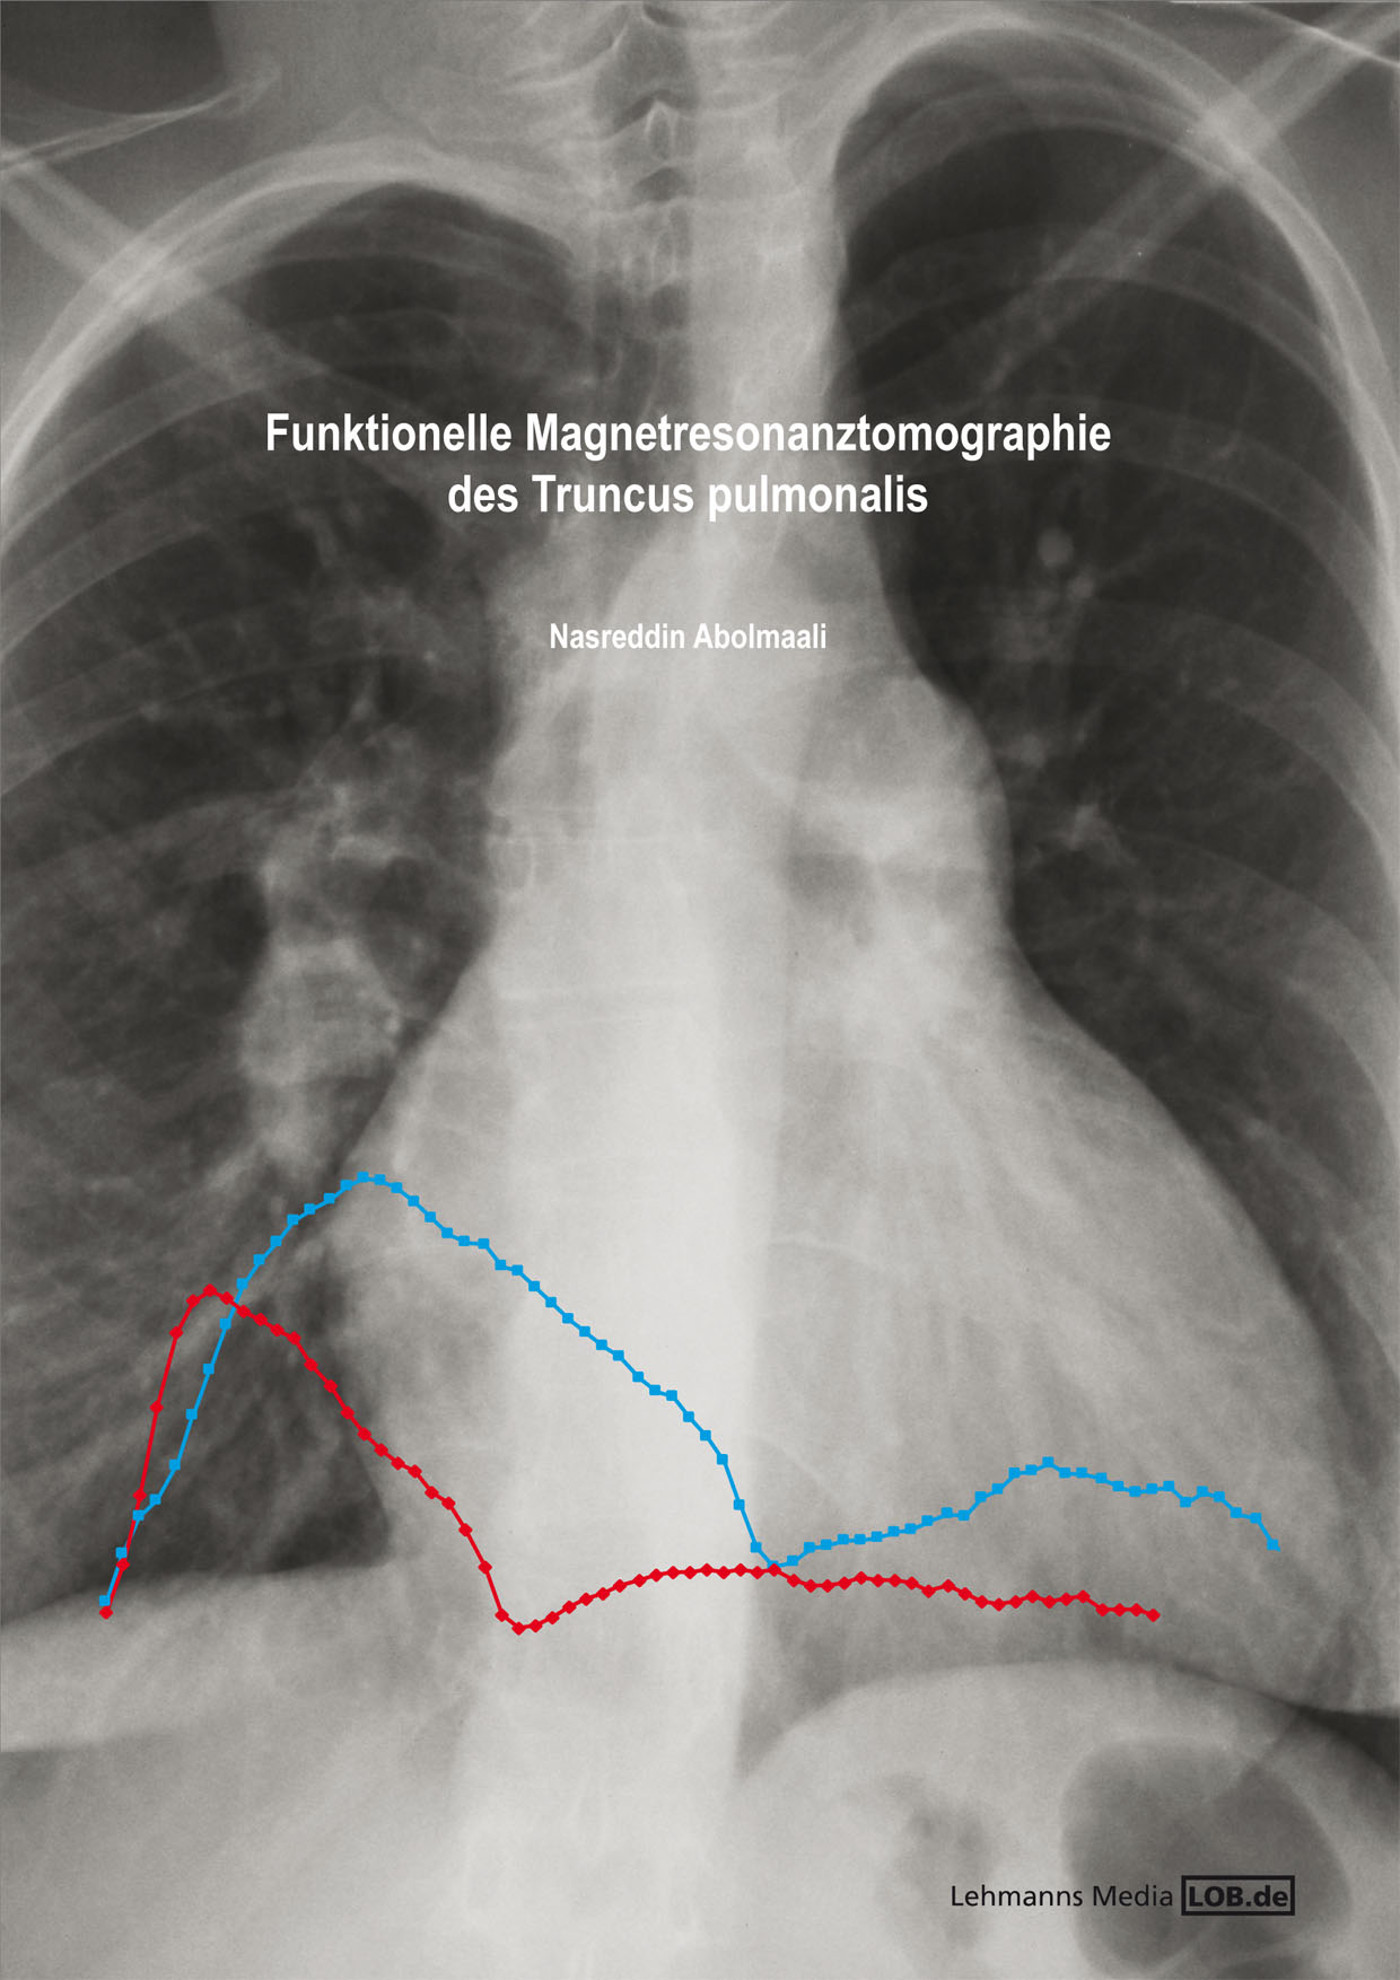

Funktionelle Magnetresonanztomographie des Truncus pulmonalis

Aus diesem Bestreben heraus ist auch das vorliegende Buch entstanden. Funktionelle Magnetresonanztomographie des Truncus pulmonalis ist ein Buch, das eine detaillierte Einführung in die Grundlagen der speziellen Anwendung der magnetresonanztomographischen Flussmessungstechnik auf die pulmonale Zirkulation gibt. Es werden die Resultate von Phantomversuchen vorgestellt und die für die Lungenstrombahn optimierten Sequenztechniken näher evaluiert und verifiziert. Daran schließt sich ein elegantes experimentelles Design zur Quantifizierung des Lungengefäßhochdruckes an, dass in seiner Art bisher einzigartig ist. Das Modell bildet die Folgen einer akuten und Widerstandsbedingten pulmonalen Hypertension reproduzierbar und reversibel ab und bietet sich damit für die Evaluation der möglichen Applikation im Patienten an. Die Idee und Durchführung dieser Untersuchungen stellt ein herausragendes Beispiel von Teamfähigkeit und interdisziplinärer Tätigkeit dar. Die Anwendung der Ergebnisse auf Patienten ist nach der statistischen Auswertung ein kleiner Schritt. Zur Validierung der Ergebnisse werden umfangreiche Normwertuntersuchungen vorgestellt, die auch eine Anwendung in der pädiatrischen Kardiologie möglich machen. Die Anwendung der entwickelten Messtechnik am Patienten schließt kongenitale Vitien, vor allem dem Ventrikelseptumdefekt, die primär pulmonale Hypertension und die sekundären Formen der pulmonalen Hypertension ein. Das neue Verfahren ist nicht nur zur Primärdiagnostik einsetzbar, sondern und vor allem auch zur Therapiekontrolle und zur Verlaufsbeurteilung geeignet.